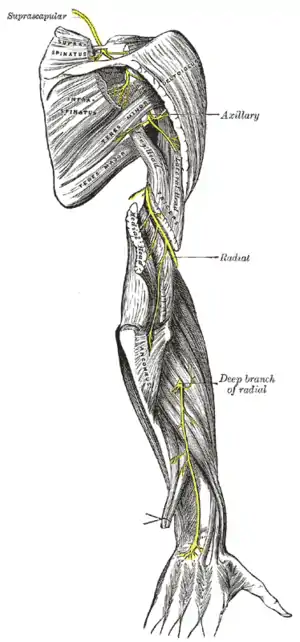

| Radial nerve compression is an example of nerve compression syndrome | |